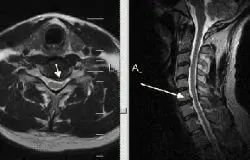

Перевагою МРТ шийного відділу хребта є те, що можна дослідити стан спинного мозку. Це дає змогу вчасно виявити так звану мієлопатію (зміна структури спинного мозку, яка призводить до зміни функції).

На знімку МРТ, який представлений нижче, видно не тільки нижній шийний відділ хребта, але і грудний. Вдале поєднання, так як шийно-грудне з’єднання часто є причиною больових відчуттів: